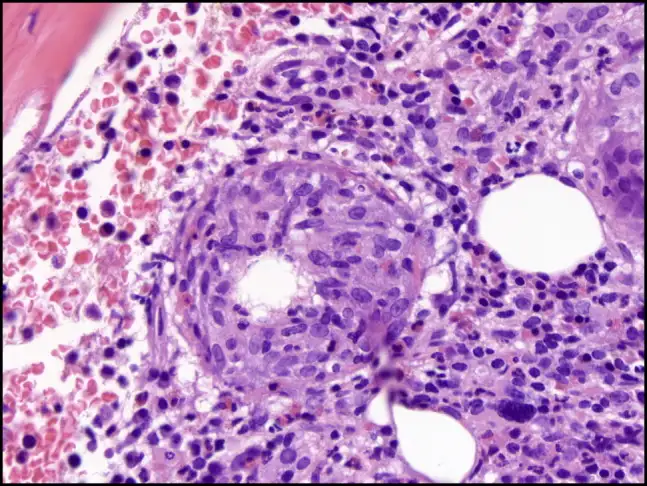

当伯内特考克斯氏体进入人体后,它的入侵策略堪称完美。它主要通过呼吸道进入,被肺泡巨噬细胞吞噬——这本应是免疫系统的第一道防线,但这种细菌却将吞噬作用变成了入侵的通道。细菌进入巨噬细胞后,被包裹在一个叫做吞噬体的膜结构中。正常情况下,吞噬体会与溶酶体融合,溶酶体内的酸性环境和消化酶会将入侵者彻底摧毁。但伯内特考克斯氏体进化出了一个惊人的对策:它不仅不逃避这种融合,反而主动促进它。它需要的正是溶酶体的酸性环境。

这种细菌携带的酸性磷酸酶可以中和吞噬体的杀伤性物质,同时它利用宿主细胞的营养在酸性的吞噬溶酶体中繁殖。这个特殊的结构被称为"考克斯氏体包含泡"(CCV)。在这个改造过的细胞器内,细菌开始疯狂复制。它们会产生一种特殊的Dot/Icm型IV型分泌系统,向宿主细胞注射数百种效应蛋白,操纵宿主细胞的信号通路,阻止细胞凋亡,确保自己的生存和繁殖。当细菌数量达到一定程度时,包含泡会膨胀到几乎充满整个宿主细胞,最终导致细胞破裂,释放出数百个新的细菌,每个都可以感染新的细胞。

然而,Q热真正令人恐惧的并非急性期,而是它的慢性化。大约1%到5%的急性感染者在数月甚至数年后会发展为慢性Q热,这是一种完全不同的疾病。病原体在体内潜伏,等待机会,最终在一些特定的部位——通常是心脏瓣膜——建立慢性感染。慢性Q热心内膜炎是最常见也最致命的表现。它发展缓慢、隐匿,患者可能只是感到疲劳、体重下降、低热、关节痛,这些症状被归咎于其他原因,直到心脏瓣膜被严重破坏。